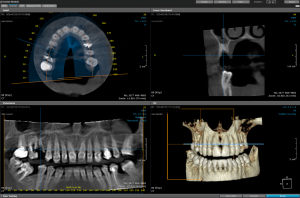

RADIOGRAFIA CBCT 3D – este o metodă de imagistică dentară și maxilo-facială care generează o imagine tridimensională a dinților, maxilarelor, sinusurilor și structurilor nervoase din zona scanată. Această tehnică utilizează un fascicul conic de raze X, o singură rotație în jurul capului pacientului și procesare computerizată pentru a crea o imagine detaliată, superioară imaginilor 2D tradiționale, esențială pentru un diagnostic precis și planificarea tratamentului. Acest tip de investigatie ofera cel mai inalt nivel al detaliilor dintre toate tipurile de radiografii.

PRET:  250 Lei / arcada

400 Lei ambele arcade

250 Lei sinusuri